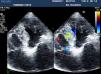

On intraoperative transesophageal echocardiography, after apical puncture, the valvuloplasty catheter impinged on the interventricular septum (Fig. 1, Video 1). When the catheter was pulled back, an iatrogenic ventricular septal defect (VSD) with a clear left-to-right shunt was detected (Fig. 2, Video 2). TA-AVI was then performed without any other complications. One year later the patient was asymptomatic and in good clinical condition. The VSD was confirmed by transthoracic echocardiography (Fig. 3, Video 3), with a Qp/Qs of 1.2.